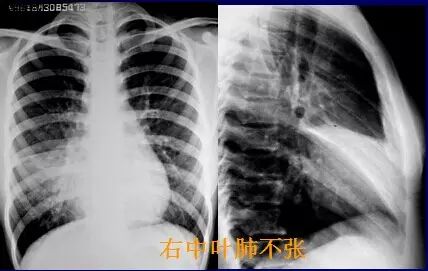

右肺中叶肺不张

肺不张x线表现图片